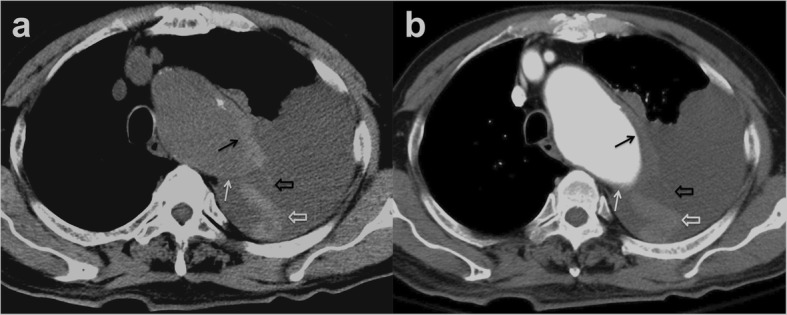

Patients 1 to 5 had initial medical treatment and stable status for 1 to 3 days suffered sudden death. Patient 1 with type A IMH (Fig. 2a, b) had sudden cardiovascular collapse 2 days later, and follow-up CT revealed aortic rupture and hemopericardium (Fig. 2c, d). Patient 2 with type B IMH had recurrent symptoms after 2 days, and follow-up CT showed adventitial tear with partial outward spillage of hematoma (Fig. 3). Patients 6 to 9 had early surgical or endovascular management recovered uneventfully. Patients 6 and 7 demonstrated ascending aorta ecchymosis with adventitial tear and intact intima at surgery (Fig. 4), and patient 8 had IMH with impending ascending aortic rupture. Pathologic examinations confirmed aortic IMH.

a Unenhanced axial CT shows a smooth eccentric defect (white arrow) in the hyper-attenuating crescentic hematoma (black arrow) along the descending thoracic aorta and (b) corresponding focal out-bulging (white arrow) of the aortic lumen with smooth obtuse edges in enhanced study, outward displacement of partially torn adventitia (open black arrow), dislodged blood clot (white open arrow), and left pleural effusion. Note the absence of intimal flap or contrast medium extravasation

Fig. 4.

a Unenhanced axial CT shows a smooth central defect (white arrow) in the hyper-attenuating crescentic hematoma (black arrows) along the ascending thoracic aorta and minimal hemopericardium. b Enhanced CT shows a smooth focal out-bulging (white arrow) of the aortic lumen corresponding to the defect on unenhanced study and non-enhancing crescentic hematoma (black arrows). Note the absence of intimal flap or contrast medium extravasation. c Surgical findings confirmed ecchymosis at the ascending aorta caused by IMH and focal aortic adventitial defect

Imaging features in patients with broken-crescent sign

A definitive CT diagnosis of aortic IMH was established based on the presence of hyper-attenuating crescentic aortic wall thickening on unenhanced CT. In a retrospective review, all nine patients exhibited a distinctive, positive broken-crescent sign in CT, with a smooth focal defect in IMH that corresponded to a smooth out-bulging of the aortic lumen with obtuse edges on the subsequent enhanced study (Figs. 2, 3, and 4). All nine patients demonstrated smooth aortic lumen with neither intima flap nor contrast medium extravasation, indicating an intact inner wall of the aorta. There were no substantial differences in maximum aortic diameter (range 42–52 mm, mean 47.0 mm vs. range 43–53 mm, mean 47.5 mm) or maximum IMH thickness (range 5–8 mm, mean 5.6 mm vs. range 4–7 mm, mean 5.3 mm) between the deceased (5/9) and surviving (4/9) patients, respectively. Of note, among eight out of 104 patients with in-hospital mortality, broken-crescent sign was retrospectively identified in five patients. Of these eight patients, three demonstrated minimal hemopericardium in CT but no other specific imaging sign for prediction of dismal outcome could be sought. Furthermore, there were no significant differences in maximum aorta diameter and maximum IMH thickness between in-hospital mortality and survival groups (49.4 ± 7.1 mm vs 46.8 ± 11.8 mm, p = 0.571; and 8.8 ± 4.2 mm vs 9.1 ± 5.8 mm, p = 0.373, respectively) (Mann-Whitney test).

To our knowledge, the application of a broken-crescent sign as a CT predictor of impending aortic rupture in patients with acute aortic IMH has not been previously reported. Differentiation of the broken-crescent sign of IMH from PAU and ULP in CT is imperative. CT of a PAU typically appears as a contrast-enhanced outpouching with acute jagged edges penetrating into the media of the aortic wall, mostly in the thoracoabdominal aorta with severe atherosclerotic disease [5, 19]. ULP is a localized, contrast-enhanced pouch in the IMH with obvious communication with the true lumen, mostly found in the ascending aorta and the aortic arch at points of great mechanical stress [5, 11, 19]. The broken-crescent sign is characterized by a smooth focal defect with obtuse edges in the hyper-attenuating crescentic hematoma, corresponding to a focal out-bulging of enhanced aortic lumen with no contrast medium leakage.

The hyper-attenuating crescent sign is seen in unenhanced CT as a localized curvilinear hyper-attenuating zone within the thrombus of abdominal aortic aneurysms and is an early sign of acute or impending rupture. It is caused by intrathrombotic hemorrhage and dissection of blood into the peripheral thrombus or aortic wall with the weakening of the support structure of the aneurysm incurring vulnerability to rupture [19, 20]. On the other hand, broken-crescent sign in IMH seems to exhibit different pathophysiological changes of the aortic wall. We postulate that acute aortic IMH may complicate with a subtle adventitial tear followed by partial outward seepage of an intramural blood clot, leading to a broken-crescent configuration on CT (Fig. 5). The CT features in patient 2 and surgical findings in patients 6 and 7 supported this postulation. Because the residual inner aortic wall remained intact, there was no contrast medium extravasation. Due to local wall thinning, focal outward bulging of the aortic lumen may have compressed on and sealing up the underlying adventitial tear temporarily; thus, the IMH spillage could be transiently alleviated, resulting in a short duration of clinical mitigation. More importantly, with such a weakened residual inner aortic wall at the site of the broken crescent, IMH patients might subject to a high risk of subsequent aortic rupture, as seen in the follow-up CT of patient 1. Notably, in our patients with positive broken-crescent sign ascribed to outward seepage of an IMH, the maximum IHM thickness (range 4–8 mm, mean 5.4 mm) was far thinner than the threshold (11 mm) used for predicting IMH complications [9, 10].